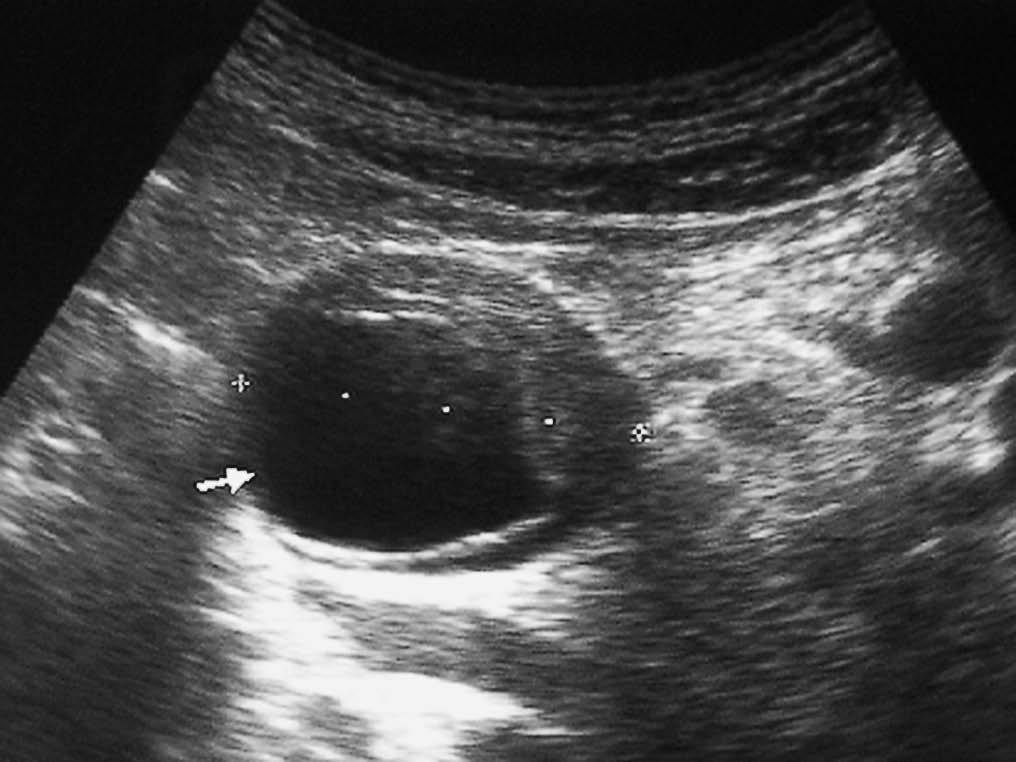

Una complicación tardía de la pancreatitis es el pseudoquiste. Puede localizarse en la pared duodenal, donde aparece radiológicamente como una lesión quística de paredes bien definidas, pudiendo producir una estenosis luminal (fig. 11).

Fig. 11--Pseudoquiste en pared duodenal. (A) Ecografía. (B) Tomografía computarizada en la que se aprecia una lesión quística (flecha) en la pared posterior de la tercera porción duodenal, que provoca compresión de la luz.